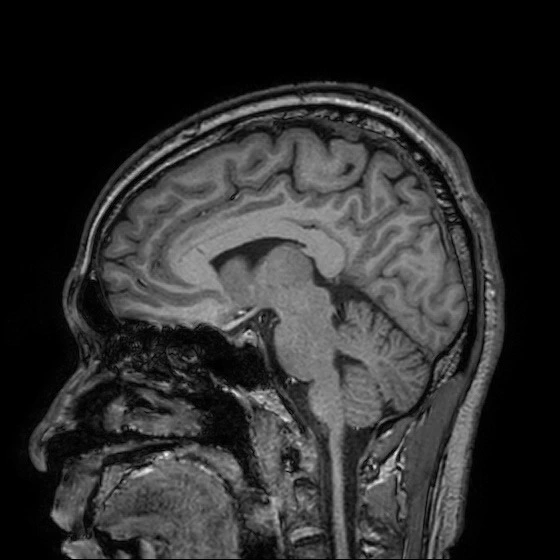

Brain MRI : 뇌 자기공명영상 - 뇌 구조 확인.

Diffusion MRI (급성기 뇌손상 확인을 위한 MRI),

Brain MRI (뇌 조직 자기공명영상),

이렇게 여러 종류의 MRI 촬영을 했네요!

영상을 보면.. 위에서, 옆에서, 밑에서.. 여러 각도에서 입체적으로 찍었어요.

과거 혈전이 있었는지 등은 일반 뇌 MRI로 확인하고..

처음 알았는데, 사진에서 왼쪽은 오른쪽이고, 오른쪽이 왼쪽이라네요.

내 뇌 구조가 이렇게 생겼구나! 정말 신기하더라고요!!

Brain MRI (Magnetic Resonance Imaging) : 뇌 조직 자기공명영상. 뇌 안쪽 구조를 사진처럼 찍어 큰 이상이 없는지 확인하는 검사.